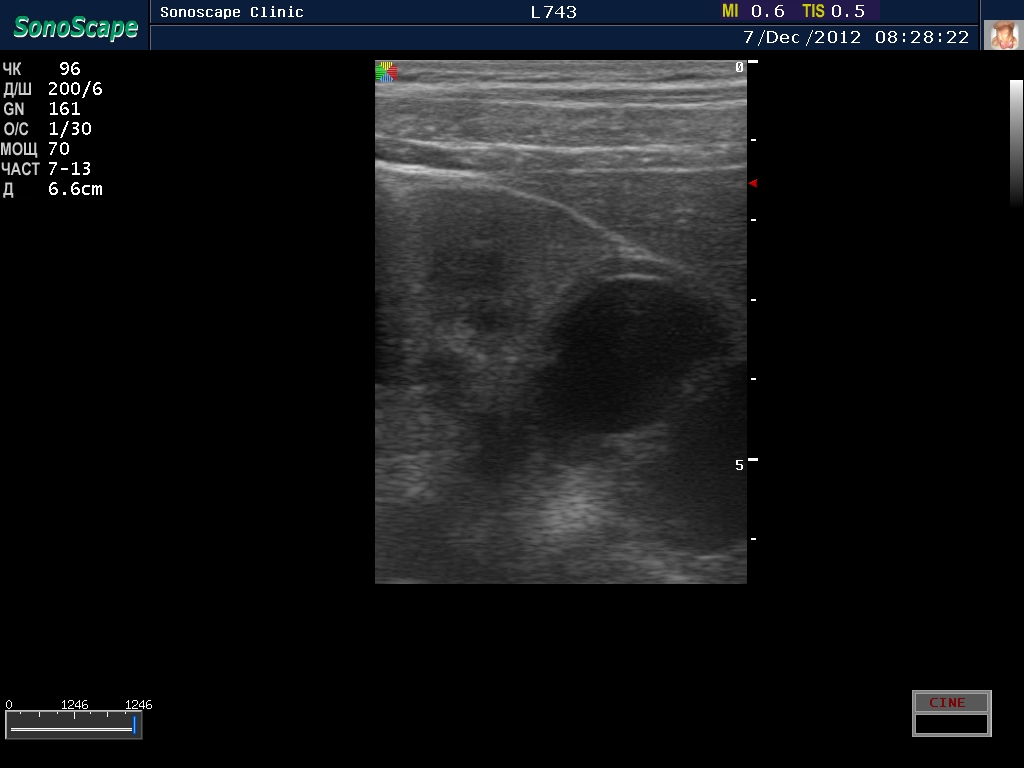

Пациент с подтвержденным туберкулезом почки

2.jpg

Видим длительно существующий гидронефроз вследствие процесса в области лоханочно-мочеточникового сегмента (видео 1), с утолщением стенок ЧЛС и истончением паренхимы почки - наиболее частая причина у взрослых - туберкулез.